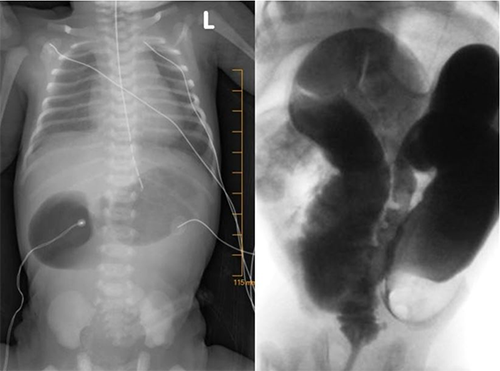

A Caucasian male was born at 39 weeks of gestation to a 20-year-old primipara via elective cesarean section secondary to polyhydramnios. DA was identified on a routine prenatal ultrasound at 31 weeks of gestation. Cell-free DNA testing revealed no fetal aneuploidy. On first day of life (DOL), the neonate developed bilious emesis, and a plain abdominal radiograph demonstrated a double bubble in the mid-abdomen without distal bowel gas (Figure 1a). The neonate was electively taken to the operating room on DOL3 for an exploratory laparotomy. Intraoperatively, a type 1 DA involving the second portion of the duodenum was repaired via a Kimura-type duodenoduodenostomy. The rest of the small bowel was unremarkable. The postoperative course was uneventful, with bowel function on postoperative day nine and discharge home at three weeks old. The patient was re-admitted four days later for constipation and intermittent vomiting and discharged two days later after symptom resolution following nonoperative management. At six weeks old, the patient was readmitted for progressive bilious vomiting, abdominal distension, obstipation, and failure to gain weight. Plain abdominal radiograph revealed dilated loops of small bowel with multiple air fluid levels. Upper gastrointestinal imaging revealed no proximal obstruction or malrotation. A lower gastrointestinal study showed a transition point at the proximal-mid sigmoid colon (Figure 1b) and FTRB revealed colonic aganglionosis.

Figure 1a and 1b. Double bubble on KUB and Transition point on contrast enema.